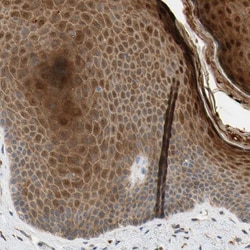

Immunogen sequence: FQSNRMDDQR CCLQEKNCHT ASTTTSSTPP KMMLKTSSVP VVSPNTDEFL DLLASSQSRR LDDQRASFSN LPGLRLTQNS QSVLSHLMTN DNKEADEDFF D Highest antigen sequence identity to the following orthologs: Mouse - 78%, Rat - 75%.

The protein encoded by this gene belongs to a family of proteins that modulate activation of G proteins, which transduce extracellular signals received by cell surface receptors into integrated cellular responses. The N-terminal half of this protein contains 10 copies of leu-gly-asn repeat, and the C-terminal half contains 4 GoLoco motifs, which are involved in guanine nucleotide exchange. This protein may play a role in neuroblast division and in the development of normal hearing. Mutations in this gene are associated with autosomal recessive nonsyndromic deafness.

| Applications | Immunohistochemistry (Paraffin), Western Blot |